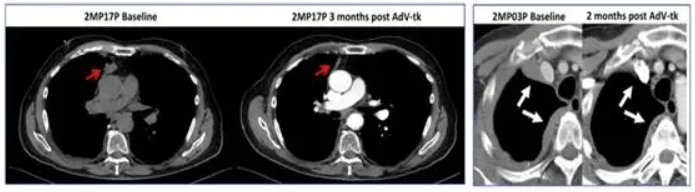

其次是生物制剂:腺病毒载体AdV‑tk。小样本的临床研究表明,胸腔内注射表达胸苷激酶基因的腺病毒载体(AdV‑tk)治疗 ,对 MPE 的疾病控制率为71%,效果和耐受性良好。